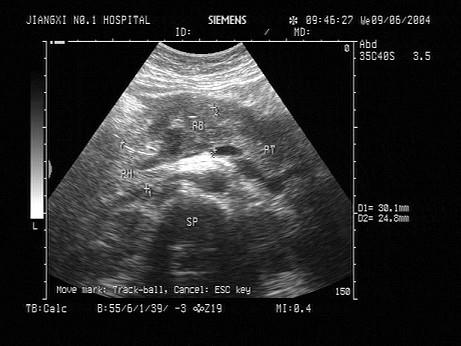

问题 患者,暴饮暴食,血淀粉酶升高,超声见胰腺体积增大,边界不清,如图所示,考虑为?(?)

选项 A.胰腺癌 B.胰腺炎 C.胰腺囊肿 D.胰腺脓肿 E.以上都不是

答案 B